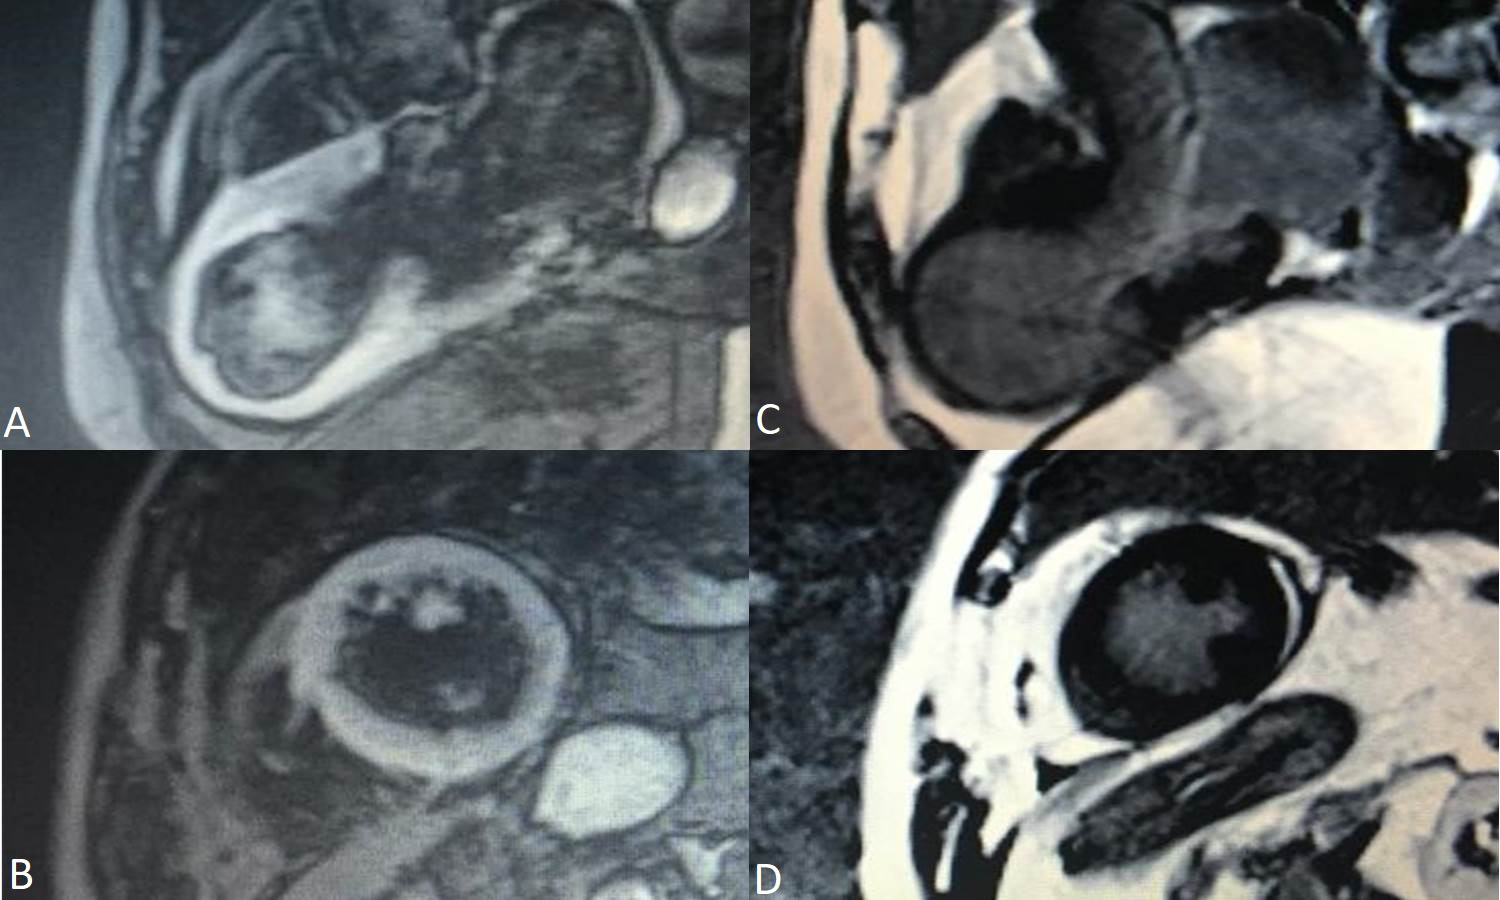

CMR using T2 weighted images is a noninvasive alternative in discovering myocardial edema. The areas of myocardial edema correlated with RWMA areas [107, 108] (Fig. 5). Studies who performed endomyocardial biopsies in Takotsubo patients proved there is inflammation in the motion abnormalities areas [109].

Fig. 5.Cardiac Magnetic Resonance Imaging of a 78 years old female patient in the acute phase of Takotsubo Syndrome. Myocardial edema can be observed in the apical regions of the left ventricle in T2 weighted images (A and B) and the lack of late gadolinium enhancement in C and D.

Generally, there is no fibrosis detected on late gadolinium enhancement (LGE) CMR. In the chronic phase, CMR follow up reveals normal ventricular function, normal regional wall motion, no edema, no necrosis and no fibrosis [110]. Even though in most Takotsubo cases there was no LGE present, LGE positive cardiac magnetic Resonance imaging (MRI) in TS were reported in a few cases [111, 112, 113]. A two-step recovery in the LV function in TS was described. The first step was the recovery of the LV systolic function and the latter one was the improvement of the diastolic one, assessed by LV peak filling rates and left atrial filling volumes [114]. CMR based strain analysis of the LV in the acute phase revealed that CMR does have prognostic value in TS patients. However, prognosis was mainly influenced by the patients’ comorbidities [115].